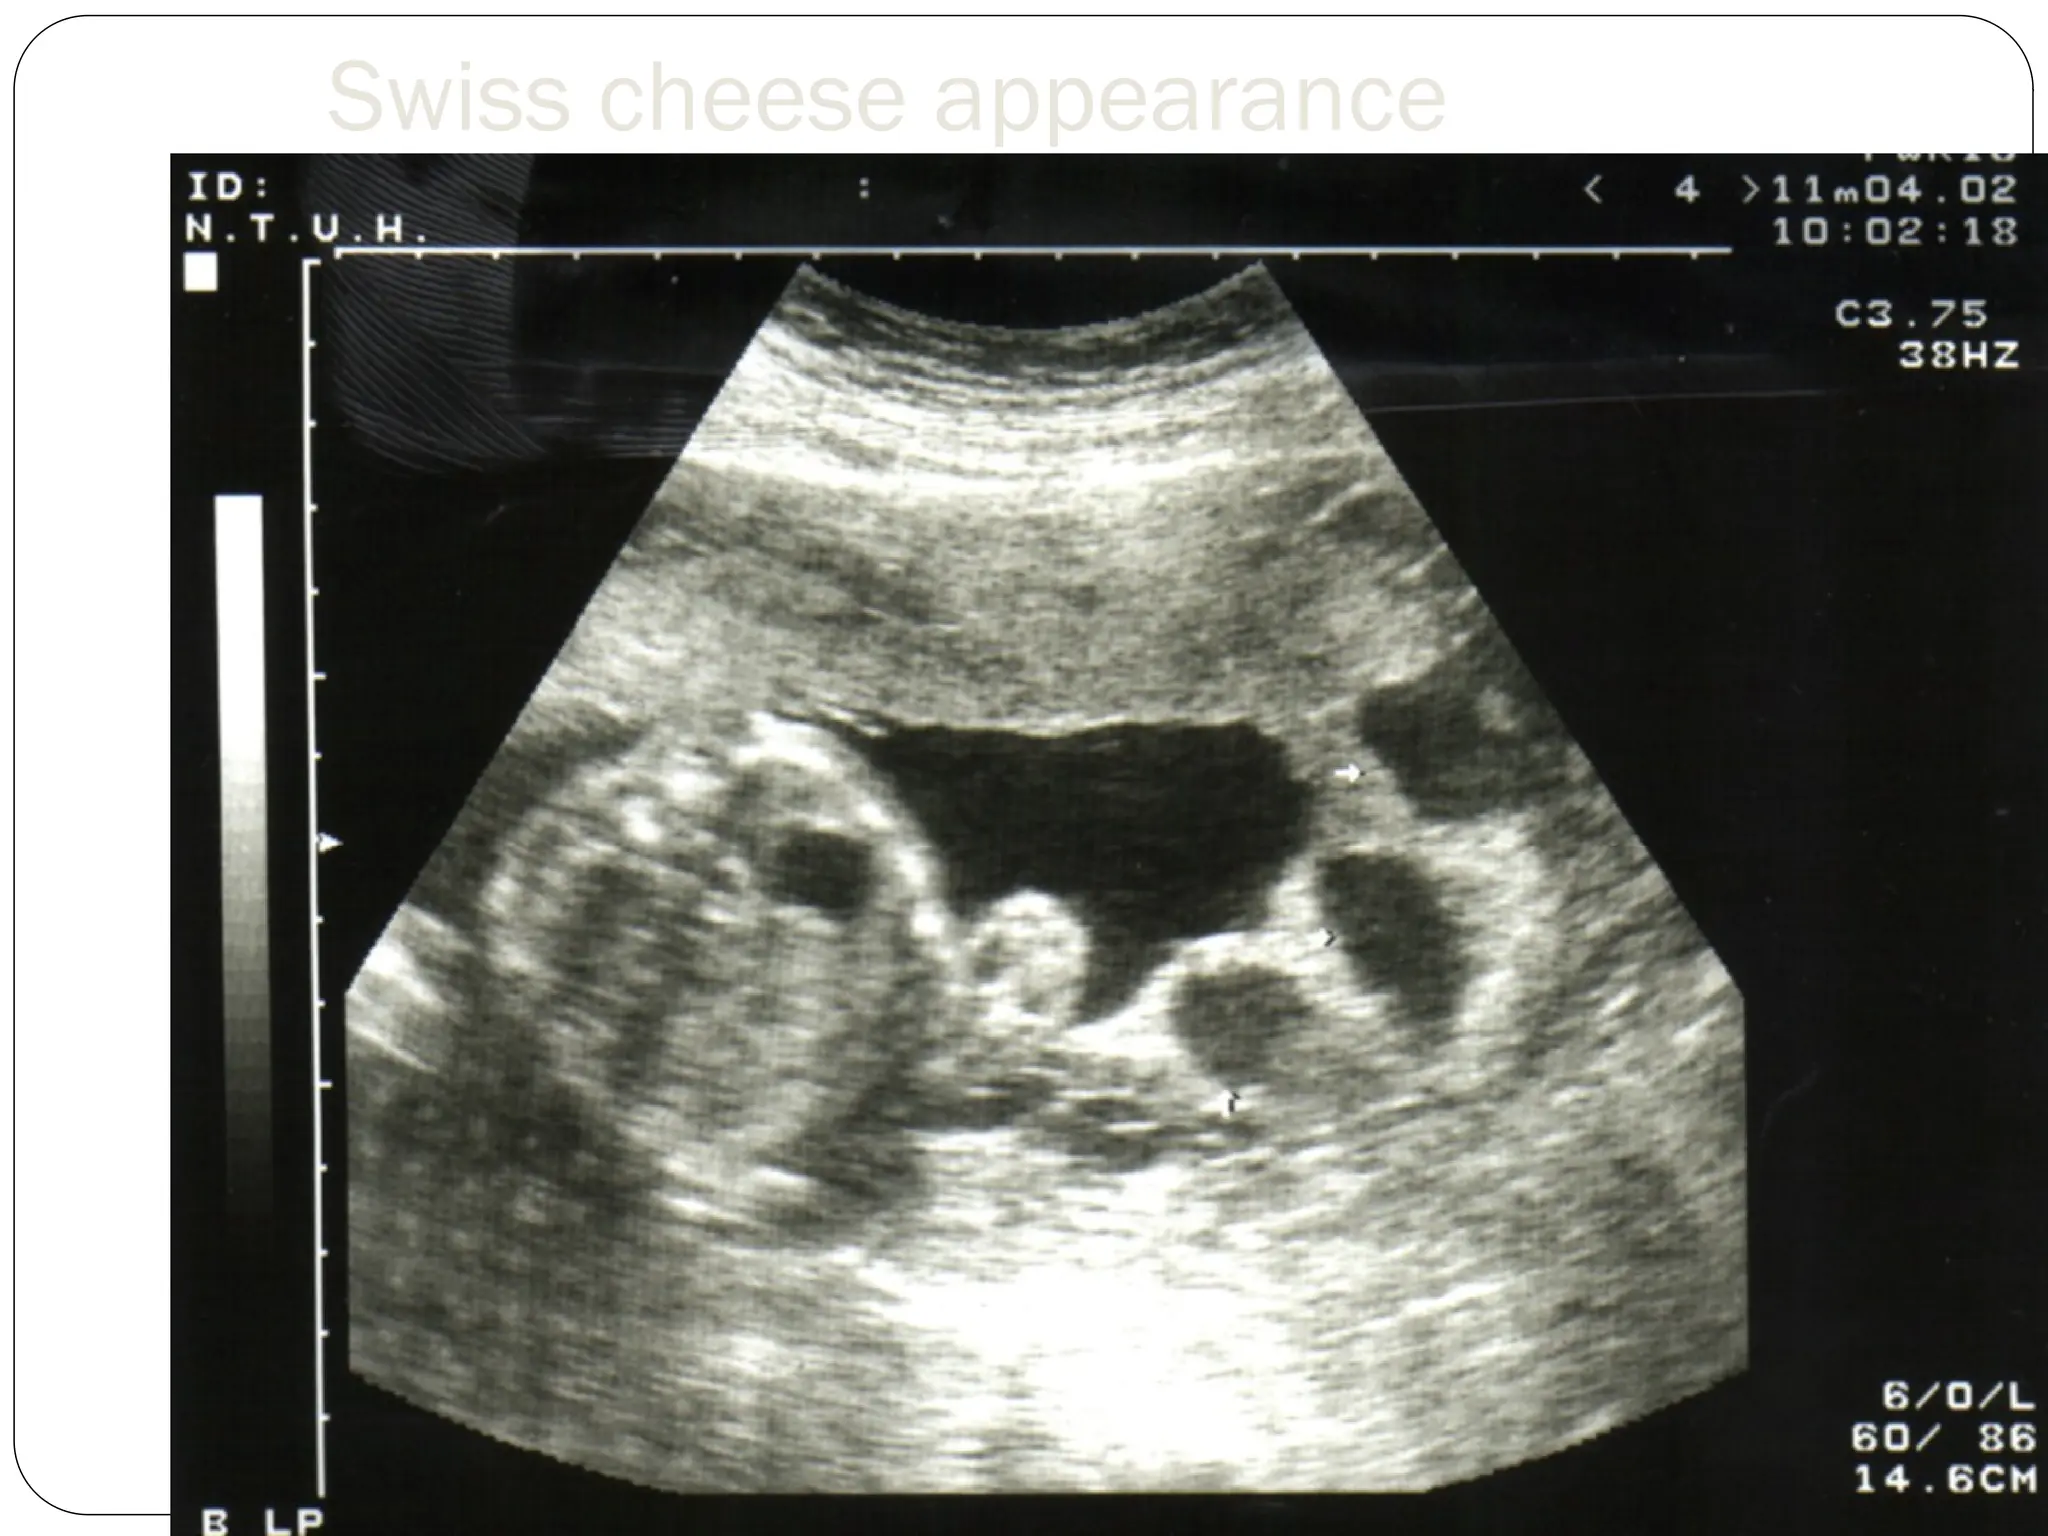

Ultrasound

loss of the normal hypoechogenic zone between

the placenta and myometrium

abnormality of the smooth interface between the

uterus and bladder

a Swiss-cheese appearance to the placenta,

pulsatile flow of maternal blood

MRI

Swiss cheese appearance